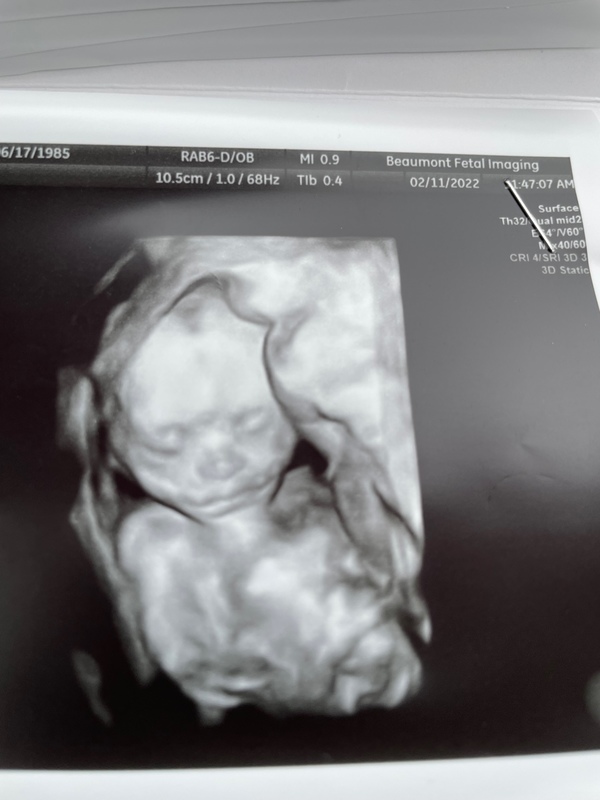

Since I've been in my second trimester I have had a lot of "little" moments that have been exciting such as when my bump started to show, feeling the baby move for the first time around week 16, and recently the anatomy scan!